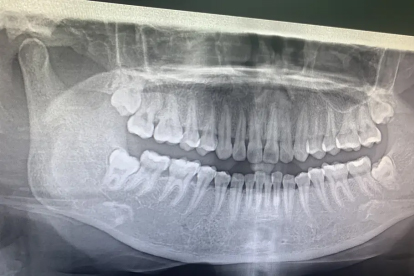

智齿发炎导致脸肿通常与局部感染扩散至周围软组织有关。智齿冠周炎可能由智齿萌出受阻、食物嵌塞、细菌感染等因素引起,炎症反应引发面部肿胀、疼痛、张口受限等症状。

智齿萌出空间不足时,牙龈瓣覆盖部分牙冠形成盲袋,易滞留食物残渣和细菌。反复刺激可导致冠周软组织充血肿胀,炎症向颊部扩散引发面部肿胀。轻度炎症可通过生理盐水冲洗盲袋缓解,中重度需口腔科医生进行牙龈瓣切除或拔牙。

智齿与邻牙间缝隙或牙龈盲袋内嵌塞食物后,细菌分解产酸腐蚀牙周组织。长期刺激可诱发急性冠周炎,伴随淋巴回流受阻导致面部浮肿。日常使用冲牙器清洁牙缝,急性期需医生用双氧水冲洗并配合头孢克洛胶囊消炎。

厌氧菌感染是智齿发炎的主要病因,细菌毒素可破坏局部毛细血管通透性,使炎性渗出物浸润面部疏松结缔组织。典型表现为患侧面颊弥漫性肿胀,触诊有波动感。需口服甲硝唑片联合阿莫西林克拉维酸钾片抗感染,脓肿形成则需切开引流。

严重冠周炎可能引发咬肌间隙、翼下颌间隙感染,炎症沿筋膜间隙扩散至面部。表现为耳前区至下颌角广泛肿胀,伴吞咽困难。需静脉注射头孢曲松钠,配合地塞米松磷酸钠注射液减轻组织水肿,必要时手术建立引流通道。